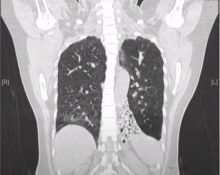

This video demonstrates the technical aspects of performing a left lower lobectomy in a patient with cystic bronchiectasis.

The severity of the pathology is notable, and it can be seen in the computed tomography imaging, as well as in the operative views. The author describes this severity as being "end-stage," as the lobe is completely fibrotic.